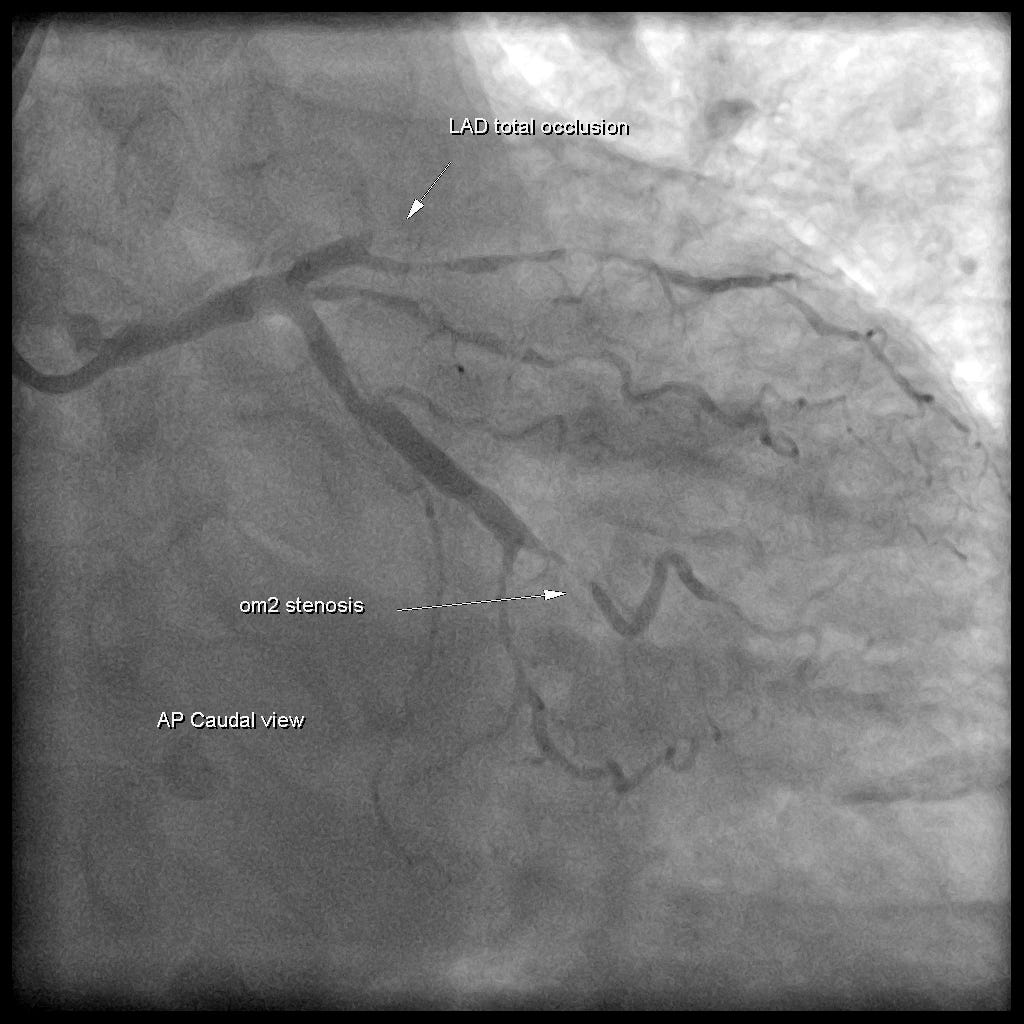

病患作了PCI顯示LAD total occlusion。

Group beats的第一跳看起來是有P wave(往V1V2對過去),偏向RBBB pattern,第二跳看起來有寬,沒有明顯P wave,可能是VPC beat,且V2V3有明顯concordant STE,代表因為有ischemia,才會產生的concordant STE。這也是OMI的證據。